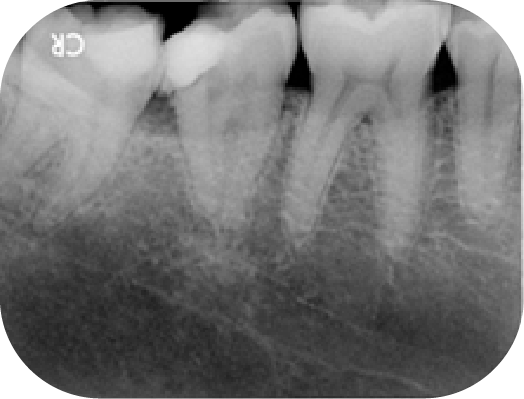

案例分享

病人左下最後兩顆大臼齒在多年前有做過根管,重新治療時因為有顯微鏡輔助可以將之前清潔不下去的根管順利處理好。